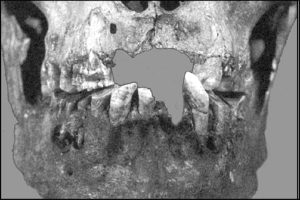

La prothèse dentaire ostéo-implantée montre à elle seule le caractère exceptionnel de ce crâne (fig.9).

En effet, la seconde prémolaire maxillaire droite a été remplacée par un pseudo-élément dentaire qui n’est ni une dent humaine, ni une dent animale, ni en ivoire, en bois mais en os. Elle est parfaitement immobile, sans aucune trace de collage.

Il s’agit d’un os de petite taille comme un os de la main, du pied ou d’une patte d’un petit mammifère dans lequel a été taillée, exécutée cette dent puis placée en bouche, mais impossible de savoir pour quelles raisons.

Le rebord alvéolaire, ne montre ni remaniement osseux, ni atrophie, ce qui laisse à penser que la restauration a été faite très peu de temps après la perte de la dent naturelle et très peu de temps avant la mort du sujet. Il existe un petit éclat alvéolaire vestibulaire qui a pu être fait lors de la pose de la dent avant ou après la mort du sujet.

Une effraction de la face externe du maxillaire (fig.12), au-dessus du rebord alvéolaire et en regard de cette dent, montre une cavité creusée dans l’os, sans aucun doute d’origine pathologique. Tout laisse à penser que cette seconde prémolaire avait présenté une périodontite apicale aiguë ou chronique, secondaire à une gangrène pulpaire. Rappelons que les autres dents ne sont pas cariées.

Il s’agit vraisemblablement d’une lésion granulomateuse ou kystique s’étant extériorisée vestibulairement.

L’orifice, ovalaire, triangulaire, est trop grand pour n’être qu’un orifice fistulaire mais ne semble pas avoir été agrandi post-mortem. Il permet d’apercevoir la partie supérieure de la restauration prothétique appointée vers l’apex, taillé en biseau. Le plancher du sinus a été respecté comme il est possible de le constater sur le crâne et sur les radiographies. Il est probable que la perte de la prémolaire soit liée à la présence de cet abcès.